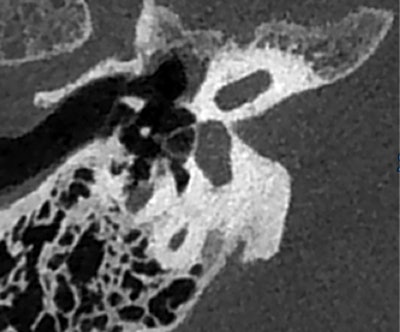

Le CBCT de l'oreille surpasse la tomodensitométrie pour analyser de petites structures telles que l'étrier. L'image est reproduite avec l'aimable autorisation du Pr Veillon."Les excellents résultats obtenus par le CBCT en font un outil indispensable pour les patients malentendants. Ne pas l'utiliser coûte plus cher", a déclaré le Pr Veillon à l'auditoire lors de la journée de formation pré JFR. "Le CBCT joue un rôle crucial dans l'évaluation des patients à opérer ou non."